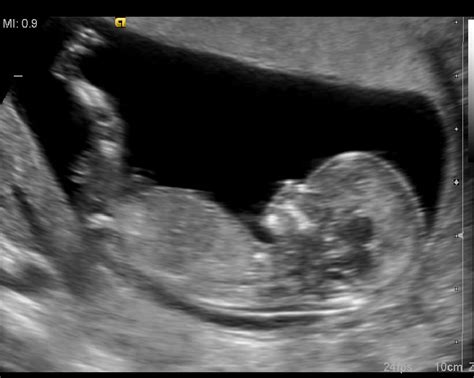

Plod se začne gibati že zelo zgodaj v nosečnosti, že okoli osmega tedna nosečnosti lahko ultrazvočno opazimo premike telesa. Vendar teh nežnih gibov, kot je upogibanje in iztegovanje telesa ali nenadzorovani gibi okončin, nosečnice v zgodnji nosečnosti še ne čutijo. Ko plod raste in se razvija, postajajo gibi vse izrazitejši in močnejši.

Prve gibe lahko nosečnica občuti že v 16. tednu nosečnosti, nekatere celo prej. Ženske, ki so že rodile, jih običajno zaznajo okoli 20. tedna nosečnosti, medtem ko lahko prvorodke te nežne premike prvič zaznajo nekoliko kasneje, pogosto okoli 20. tedna ali celo kasneje. Sprva so gibi zelo nežni, mamice jih opisujejo kot žgečkanje v spodnjem delu trebuha, plahutanje, podobno kot pri premikanju črevesja. Občutek je individualen za vsako žensko. Nekatere ga opisujejo kot pokanje mehurčkov ali nežno migetanje.